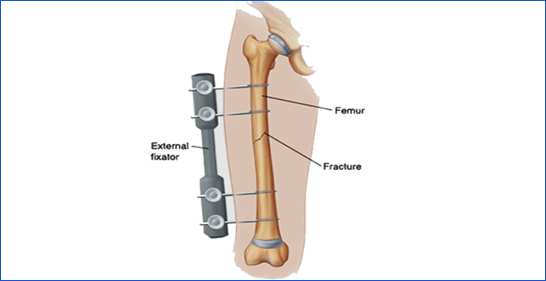

3. Femur Shaft Fracture

A break along the length of the thigh bone.

Icon Cause: High-impact trauma, car accidents, or falls from heights.

Icon Symptoms: Severe pain, inability to bear weight, visible deformity.

Icon Treatment: Surgery with rods or plates, followed by rehabilitation.